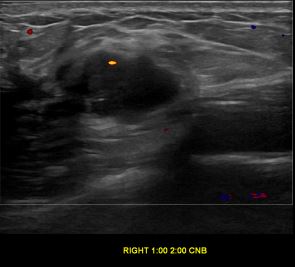

상기환자는 외부검사상 조직검사 권유받고 내원하신 40대 초반

여성분으로 의심스러운 우측유방혹 조직검사 시행해 유방암으로 진단되었습니다